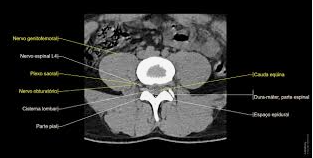

3. Coluna Lombar

5 vértebras (L1-L5), corpos largos, processos transversos longos, lordose acentuada. Discos espessos, forames intervertebrais amplos. Em TC: focar em facetas articulares, ligamento flavum, conus medullaris em L1-L2.

Achados Normais

Paisagem Montanhosa

Coluna Lombar

Esquema anatômico da coluna cervical.

Arquitetura Moderna

Corte Lombar.